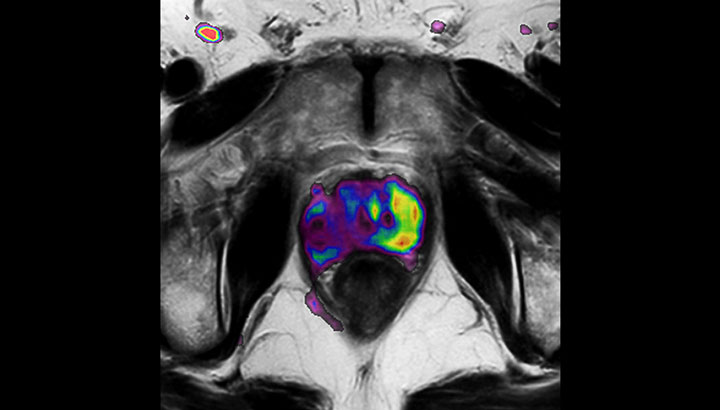

The ability to tune contrasts can provide even more valuable information about tumor characteristics and tumor extent to facilitate enhanced delineation, and also provides possibilities for dose boosting strategies.

In addition to anatomical imaging, MRI offers the ability to obtain functional information that is beneficial for tumor detection and delineation, and for response monitoring.

Diffusion-weighted imaging (DWI) for example depicts areas of high signal intensity in soft tissues that are indicative of the restricted water mobility (i.e., diffusion) of a tumor and can also be used to identify lymph nodes. Changes in the tissue’s or lesion’s apparent diffusion coefficient (ADC) can provide insights that help predict the tumor’s response to radiotherapy.